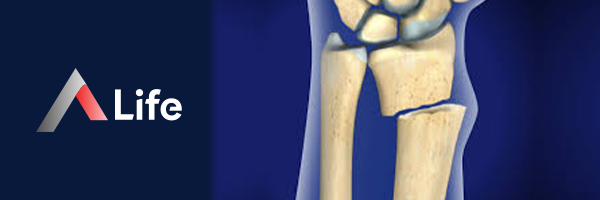

Radius Nedir?

Radius kemiği, uzun kemiklerin genel yapısına sahiptir ve üç ana bölümden oluşur:

1. Proksimal Uç (Üst Uç):

• Baş: Disk şeklinde bir yapıya sahiptir ve humerus kemiğinin (kol kemiği) kapitulumu ile eklem yapar. Ayrıca, ulna kemiğinin radial çentiği ile de eklem yaparak dirseğin dönme hareketine olanak tanır.

• Boyun: Başın altında bulunan dar bir bölgedir.

• Radial Tüberositas: Boynun altında bulunan ve biceps brachii kasının (pazı) bağlandığı çıkıntıdır.

2. Şaft (Gövde):

• Radius'un uzun ve hafifçe kavisli kısmıdır.

• Üst kısımda ince, alt kısımda daha kalındır.

• Pronator teres ve supinator gibi ön kol kaslarının bağlandığı yerler bulunur.

3. Distal Uç (Alt Uç):

• El Bileği Eklem Yüzeyi: El bileğindeki karpal kemikler (skafoid ve lunat) ile eklem yapar.

• Stiloid Çıkıntı: Distal ucun lateral (başparmak) tarafında bulunan çıkıntıdır.

• Ulnar Çentik: Ulna kemiğinin başı ile eklem yapan çentiktir.